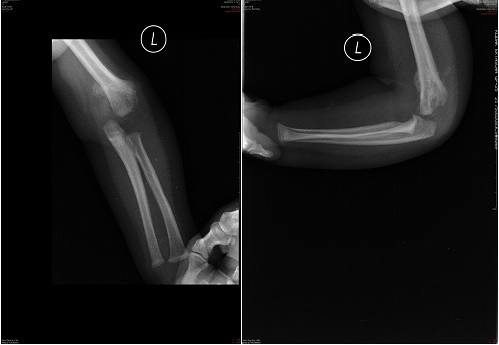

Dziecko w wieku 17 miesięcy upadło z własnej wysokości doznając urazu lewej kończyny górnej. Lekarz w Izbie Przyjęć po ocenie klinicznej stwierdził zniekształcenie łokcia i zlecił wykonanie badania radiologicznego łokcia w dwóch projekcjach. Zaproponuj właściwe rozpoznanie:

Dziecko w wieku 8 lat trafiło do Izby Przyjęć po urazie prawego przedramienia. Lekarz zlecił wykonanie badania radiologicznego, które wykazało złamanie kości łokciowej z zagięciem odłamów ku przodowi i przednim zwichnięciem głowy kości promieniowej. Zaproponuj rozpoznanie i sposób leczenia:

Dziecko w wieku 8 lat doznało urazu przedramienia i łokcia prawego. Zastosowano gips ramienny przez 6 tygodni. Po tym czasie zdjęto unieruchomienie i zastosowano leczenie usprawniające. Po 3 miesiącach lekarz w Poradni Ortopedycznej stwierdził brak poprawy zakresu ruchów i wykonał zdjęcie radiologiczne, na których rozpoznał zastarzałe zwichnięcie głowy kości promieniowej po przebytym złamaniu typu Monteggia - typ I wg Bado. Zaproponuj dalsze postępowanie lecznicze:

8-letni chłopiec doznał urazu przedramienia. Lekarz w Izbie Przyjęć stwierdził zniekształcenie przedramienia i stawu łokciowego. Zaplanuj wykonanie dalszych badań:

Złamanie typu Monteggia to złamanie: